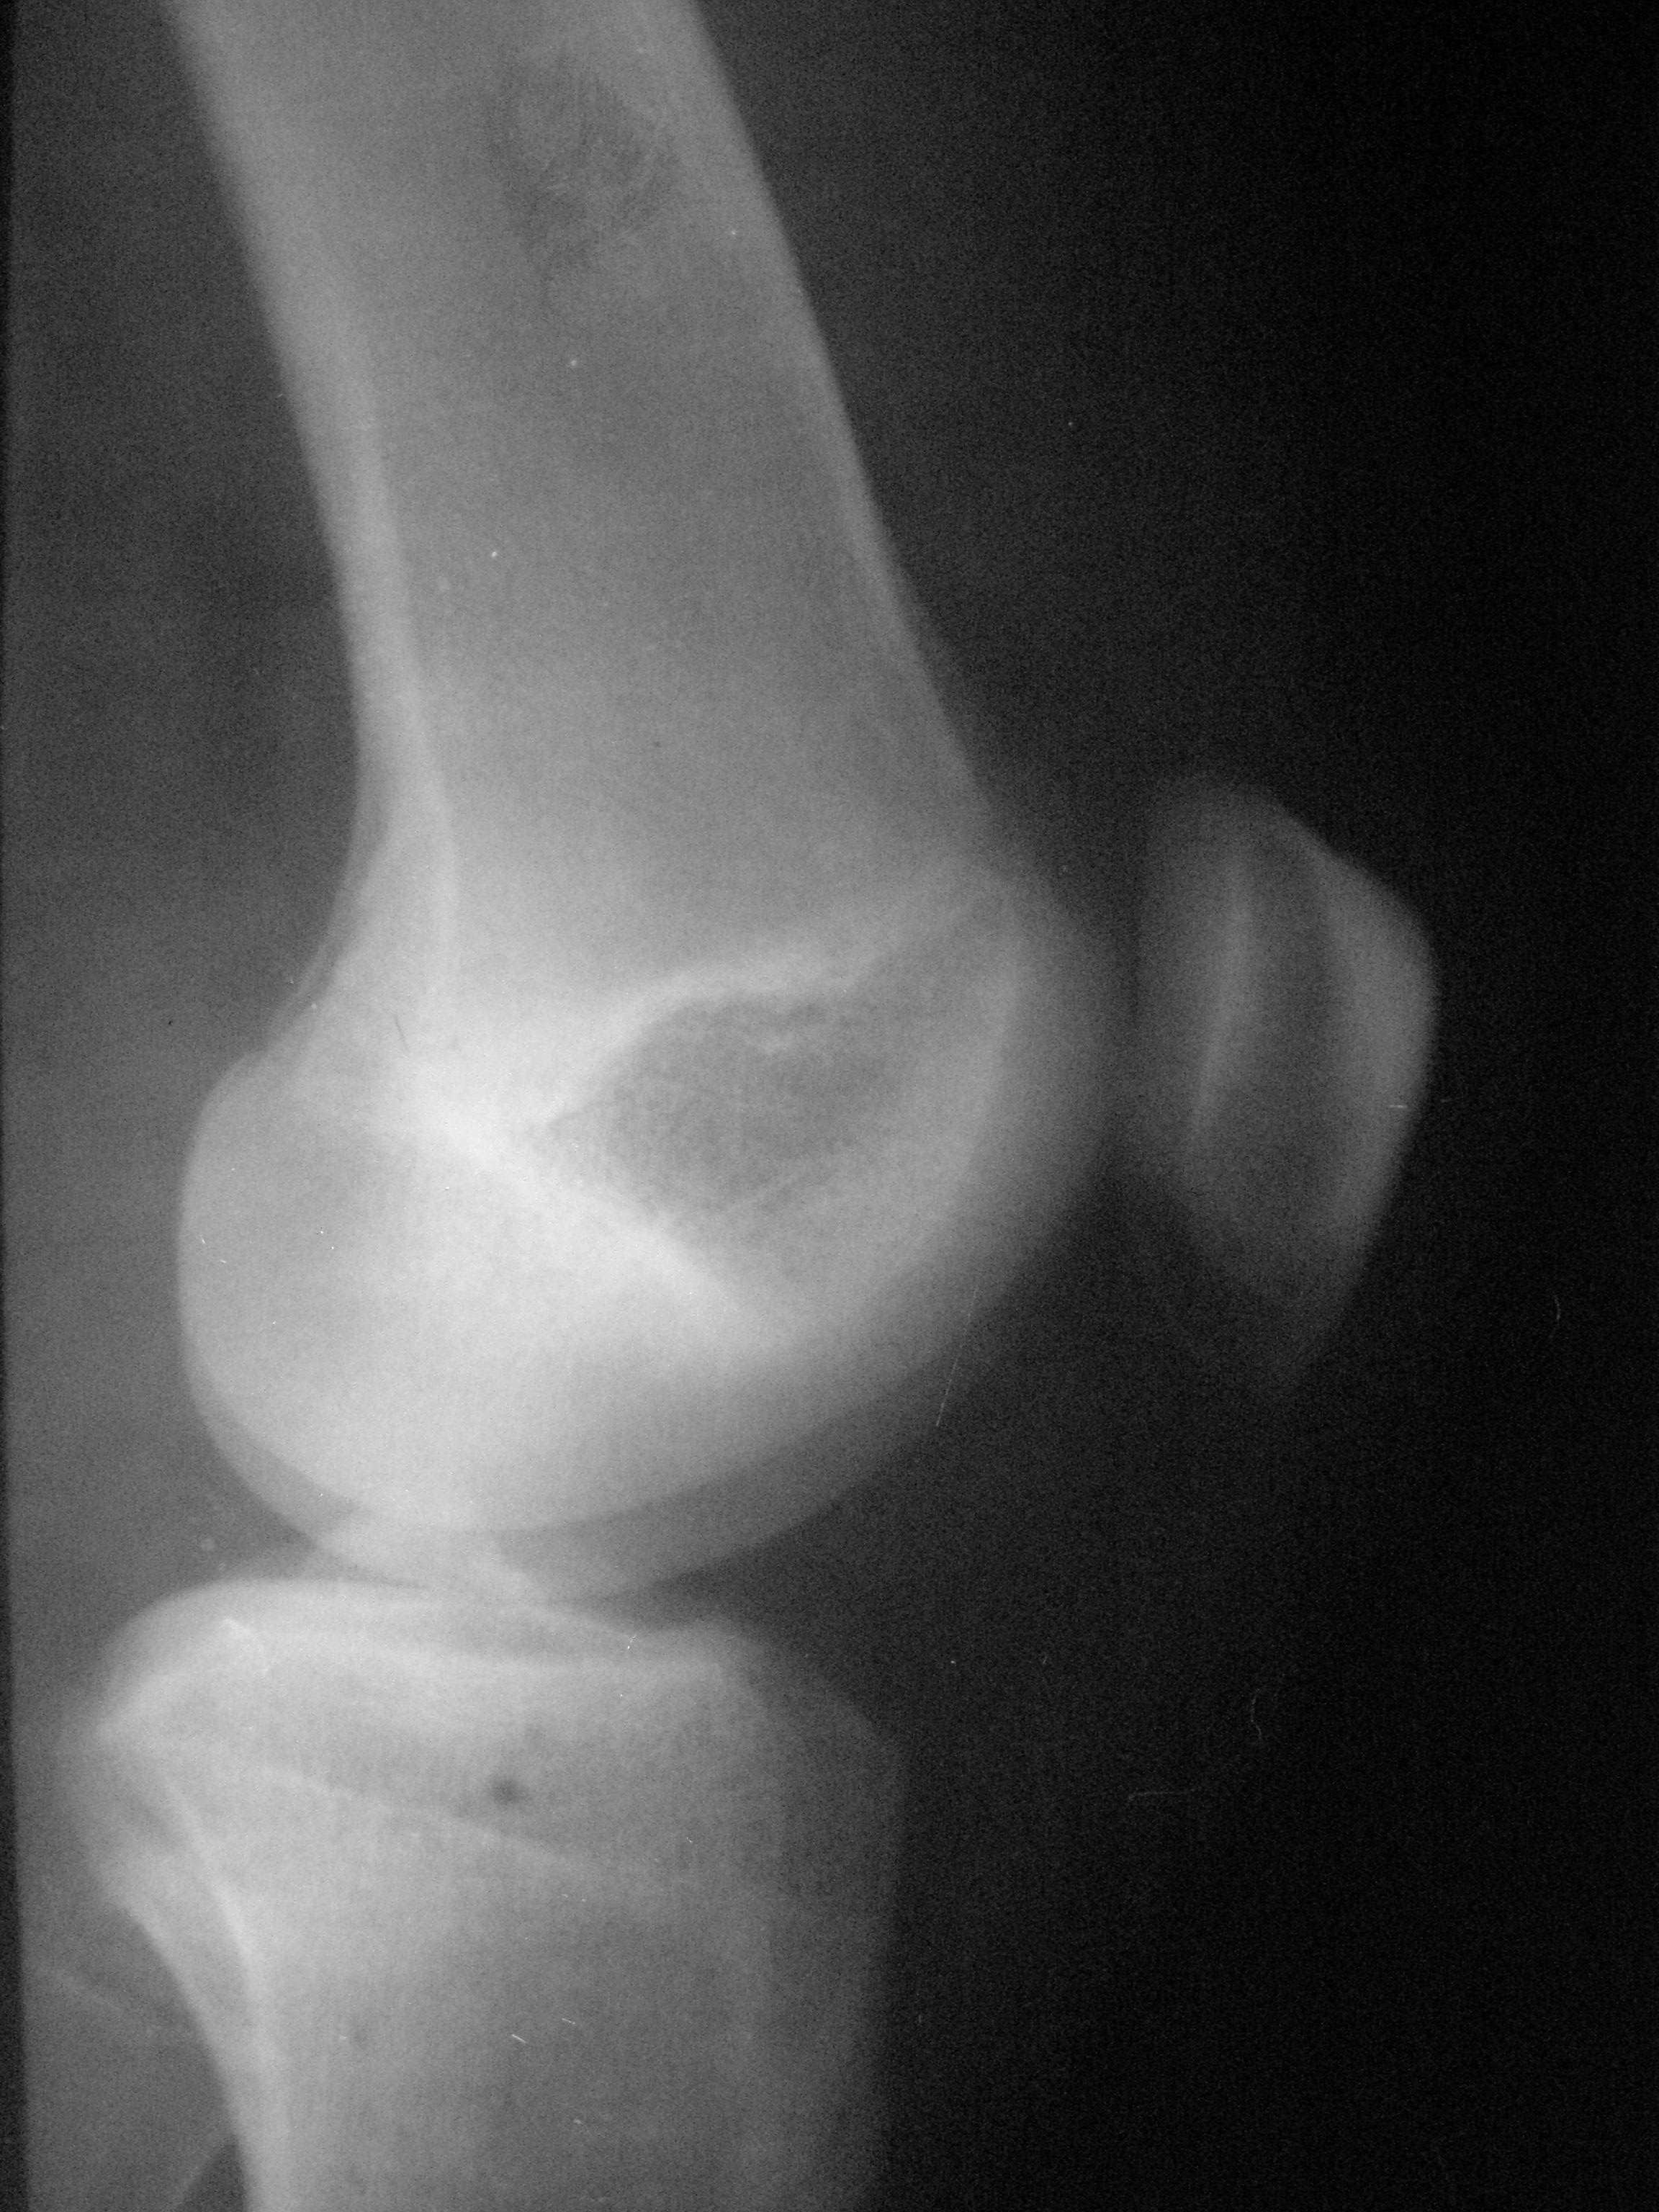

М.15лет. Жалобы на периодическую жгучую боль в L коленном суставе,после умеренной нагрузки, беспокоит 1мес. https://radiomed.ru/sites/default/files/styles/case_slider_image/public/user/15746/p4090030.jpg?itok=kvBtdL0b https://radiomed.ru/sites/default/files/styles/case_slider_image/public/user/15746/p4090031.jpg?itok=wUf85A5t ID:50918 Mon, 09/04/2012 - 17:48 #1 nelly Offline Last seen: 11 years 3 months ago Joined: 11.07.2011 - 19:19 Posts: 328 мне видится какой-то участок разряжения костной ткани в н3 диафиза БК..,не знаю как стрелочки ставить,а то отметила бы,а суставе артроз похоже имеется Mon, 09/04/2012 - 19:51 #2 ДокRg Offline Last seen: 12 years 6 months ago Joined: 30.03.2011 - 20:05 Posts: 105 nelly wrote: мне видится какой-то участок разряжения костной ткани в н3 диафиза БК..,не знаю как стрелочки ставить,а то отметила бы,а суставе артроз похоже имеется Я бы назвал этот участок разряжения - пятном Лудлофа( норма). А вот для исключения болезни Осгуд-Шляттера сделал бы снимки б/берцовых костей обеих ног с большим захватом. Mon, 09/04/2012 - 20:40 #3 maker4ik Offline Last seen: 8 years 9 months ago Joined: 19.10.2011 - 17:49 Posts: 2682 ДокRg wrote: nelly wrote: мне видится какой-то участок разряжения костной ткани в н3 диафиза БК..,не знаю как стрелочки ставить,а то отметила бы,а суставе артроз похоже имеется Я бы назвал этот участок разряжения - пятном Лудлофа( норма). А вот для исключения болезни Осгуд-Шляттера сделал бы снимки б/берцовых костей обеих ног с большим захватом. Пятно Лудлофа в эпифизе находится, а nelly про н/3 диафиза говорит. Mon, 09/04/2012 - 20:56 #4 Любовь С. Offline Last seen: 9 years 8 months ago Joined: 23.12.2010 - 01:58 Posts: 2324 Переснять диафиз в 2 проекциях. "Предоставляя весь смысл и совершенство в распоряжение одного только Бога, вы избавляете себя от бездны хлопот." Джон Уитборн. Mon, 09/04/2012 - 21:00 #5 nelly Offline Last seen: 11 years 3 months ago Joined: 11.07.2011 - 19:19 Posts: 328 да,да,я именно про это пятно,которое maker4ik указал стрелкой. Mon, 09/04/2012 - 21:17 #6 И.Бондаренко Offline Last seen: 17 hours 14 min ago Joined: 13.09.2011 - 22:55 Posts: 9209 Есть незначительное снижение медиальной суставной щели. А так бы написал норму. Tue, 10/04/2012 - 03:23 #7 Демчев Валентин... Offline Last seen: 7 years 10 months ago Joined: 08.02.2011 - 15:40 Posts: 445 Никакой болезни Осгуда-Шлаттера здесь нет. Переснять диафиз в 2-х проекциях, опять какой- нибудь метафизарный корковый дефект.

мне видится какой-то участок разряжения костной ткани в н3 диафиза БК..,не знаю как стрелочки ставить,а то отметила бы,а суставе артроз похоже имеется

Пятно Лудлофа в эпифизе находится, а nelly про н/3 диафиза говорит.

Есть незначительное снижение медиальной суставной щели. А так бы написал норму.

Никакой болезни Осгуда-Шлаттера здесь нет. Переснять диафиз в 2-х проекциях, опять какой- нибудь метафизарный корковый дефект.